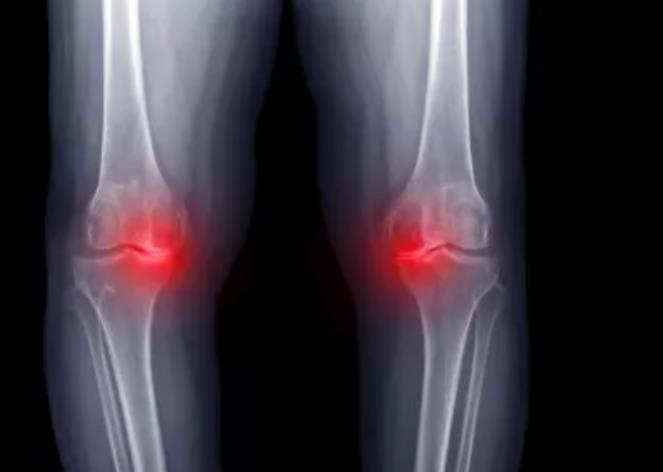

作品所属领域:药学

徐玉琴 康复医学科 主治医师